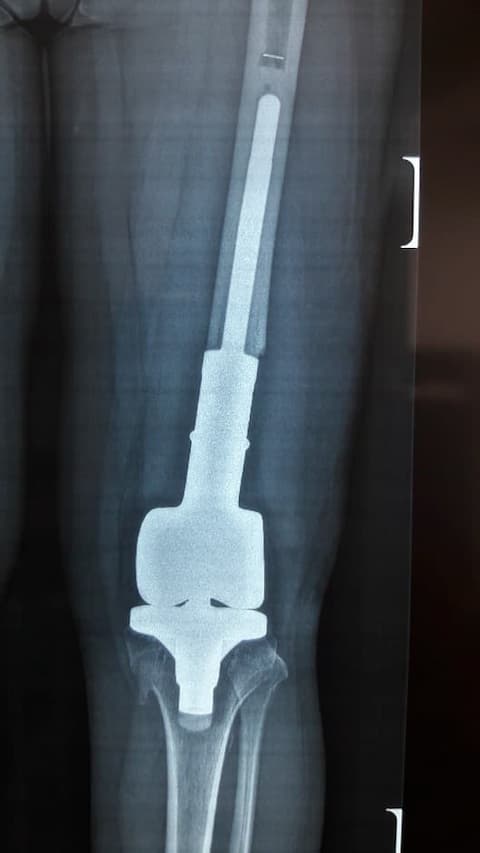

Сэргээн засах мэс засал: Өвдөгний үе сэргээх тусгай протез суулгах мэс засал.

Үе дайрсан ясны анхдагч хавдар, ясны дутмагшлын үед хийгдэх мэс засалimg24Үе дайрсан ясны анхдагч хавдар, ясны дутмагшлын үед хийгдэх мэс засалimg25

Зураг 2. Мэс заслын дараах рентген зураг. Эгц урд, хажуугаас авсан байдал

Өвдөгний үений шөрмөсөн холбоосууд үрэвслийн улмаас бүрэн гэмтсэн Дунд чөмөг - шилбэ ясны дутмагшилтай учир дунд чөмөг-өвдөгний хавдрын протез сонгон суулгасан. Энэ дунд чөмөг-өвдөгний хавдрын протез нь мөн hinge system- тэй.